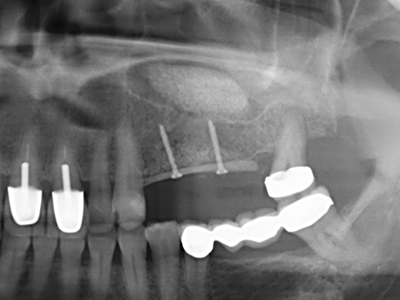

Fig. 13: Adequate irrigation with the 4-mm residual bone width is essential for this 52-year-old patient during the bone splitting.

Fig. 14: Placement of four tapered RSX implants (Bego Implant Systems, Bremen).

Fig. 15: The one-year follow-up x-ray examination shows stable conditions at the bone level.

Fig. 16: The intraoral conditions are also stable with embedding of the implants in keratinized gingiva.